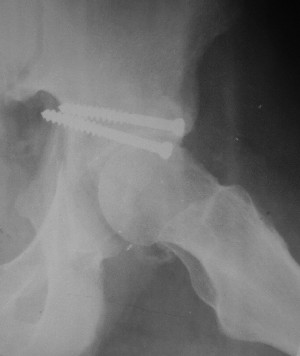

Послеоперационный снимок прямой 5/05/03

Послеоперационный снимок боковой 5/06/03

Больной 18 мая 2003 года в автоаварии получил перелом левой вертлужной впадины, вывих бедра. Госпитализирован в один из стационаров области.Вывих вправлен. В последствии бедро вывихивалось еще дважды. На консультацию был представлен снимок от 19.05.03г., больной переведен к нам 3.06.03г. Снимок при поступлении - перелом впадины, задне-верхний вывих бедра. 05.06.2003 г. выполнено открытое вправление вывиха левого бедра и остеосинтез стенки вертлужной впадины двумя винтами. Послеоперационный период без осложнений. Объем движений в левом тазобедренном суставе восстановился полностью. Выписан на амбулаторное лечение в удовлетворительном состоянии с рекомендациями 3 месяца ходить на костылях без нагрузки на оперированную конечность. На контрольных рентгенограммах левого тазобедренного сустава 13.10.2003 г. - признаки консолидации перелома; плотность, форма головки и состояние суставных поверхностей удовлетворительные. Разрешена дозированная осевая нагрузка, на конечность с использованием дополнительной опоры. 19.12.2003 г. больной обратился с жалобами на боли в левом тазобедренном суставе. На рентгенограммах левого тазобедренного сустава 19.12.2003 г., 20.02.04г. - асептичекий некроз головки бедра. 5.04.04г. - эндопротез. Сейчас ходит без трости, не хромает. Особенность эндопротезирования - при удалении винтов прослежена линия перелома заднего края впадины и предложено установить чашку несколько меньшего диаметра, чтобы она была покрыта несломанной частью.